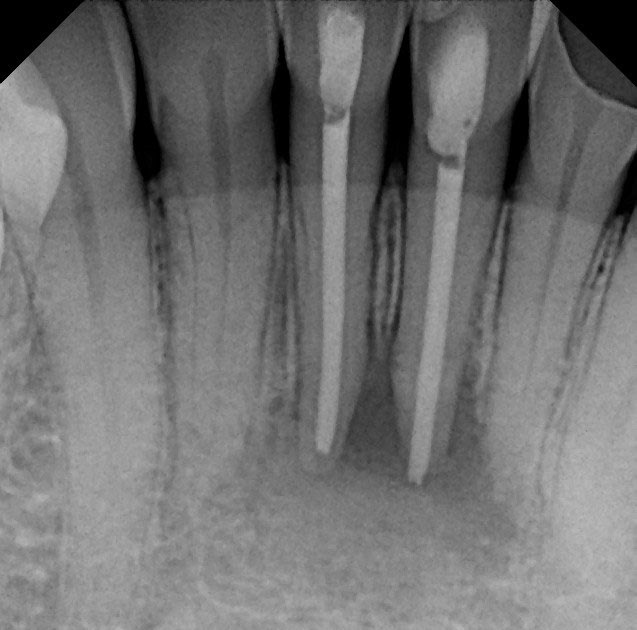

From www.researchgate.net

(PDF) Apicoectomy for Periapical Lesion Treatment after Post Endodontic Endodontic Apicoectomy Your dentist may recommend an apicoectomy if you have: in this detailed guide to apicoectomy surgery, highly esteemed specialist endodontist mr corneliu gherasim offers expert insight on when the procedure is required and how it is performed. what is an apicoectomy? An apicoectomy is a minor dental surgery that removes the tip of a tooth’s root, called the. Endodontic Apicoectomy.

From pocketdentistry.com

Classifications and Management of Endodonticperiodontal Lesions Endodontic Apicoectomy An apicoectomy is a minor dental surgery that removes the tip of a tooth’s root, called the apex. in this detailed guide to apicoectomy surgery, highly esteemed specialist endodontist mr corneliu gherasim offers expert insight on when the procedure is required and how it is performed. Your dentist may recommend an apicoectomy if you have: an apicoectomy is. Endodontic Apicoectomy.